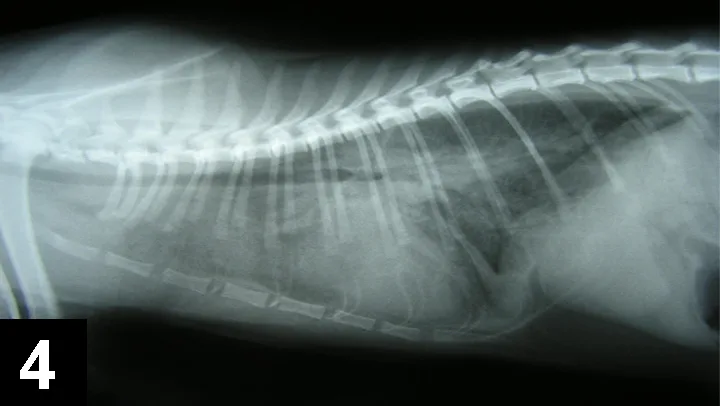

A lateral radiograph of a canine thorax shows the ribcage, spine, and heart silhouette, with clear delineation of the lungs and diaphragm. The image highlights the anatomical structures for evaluation of respiratory and cardiovascular health.

Figure 4. Lateral thoracic radiograph of a patient with pulmonary edema secondary to fluid overload.